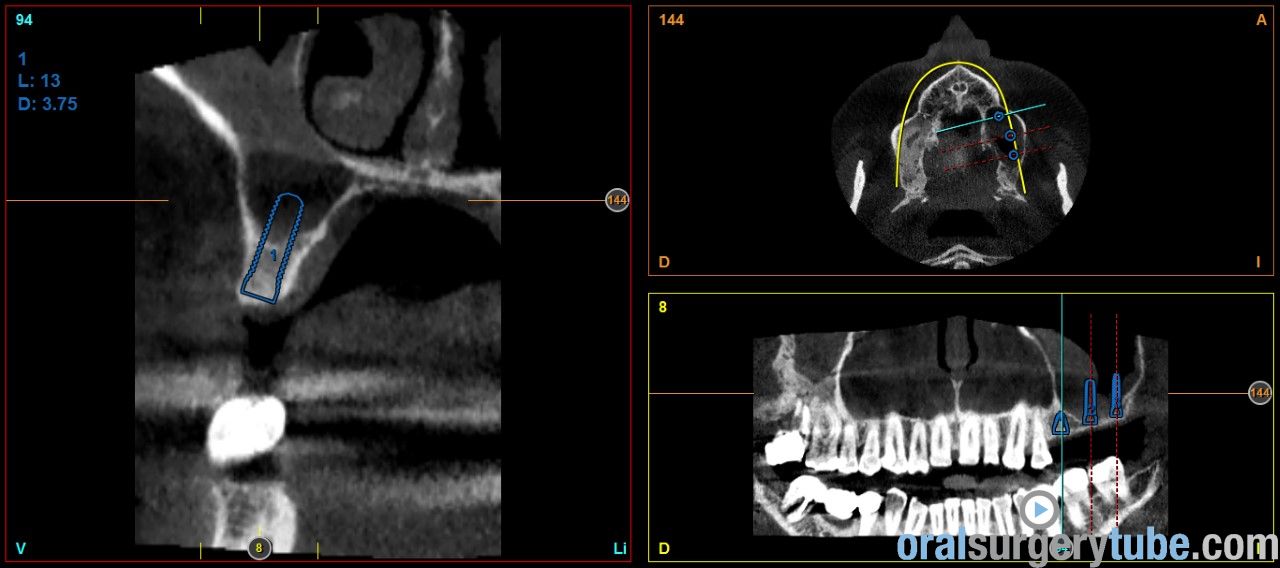

Engrosamiento mucoso

Estimados compañeros, me gustaria saber como abordaríais el seno izquierdo el cual como veis presenta engrosamiento mucoso. Haríais tratamiento previo? Gracias de antemano

Que opináis de dar un corticoide vía oral? Como la dexametasona?. Por cierto repetí el tac después de hacer la elevación derecha y de dar antibiótico y la verdad que el engrosamiento del sebo izquierdo a cambiado más bien poco por no decir que incluso se ha engrosado un poco más, pero eso sí, el paciente no refiere haber tenido en toda su vida síntomas de sinusitis ni alergia, imagino que la causa es la desviación que se ve del tabique hacia la izquierda y la concha bullosa del cornete medio, de verdad no se q hacer, si abordar el seno así ( ya que el paciente no tiene síntomas ) o derivarlo a un otorrino.Tampoco me parece exagerado el engrosamiento, qué opináis?

Os envío imagenes. Se aprecia engrosamiento de la membrana del seno maxilar izdo.